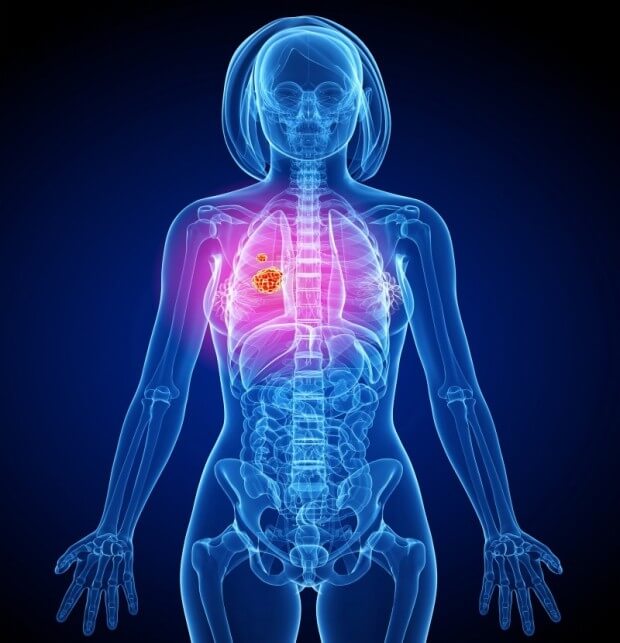

숨 쉬는 순간마다 위협하는 무서운 적, 폐암. 전체 암 사망 원인 1위를 차지하며, 진단 후 5년 내 사망률이 7~80%에 달하는 치명적인 질병입니다. 하지만 조기 발견 시 90%라는 놀라운 완치율을 기대할 수 있다는 사실, 알고 계셨나요?

오늘은 폐암이라는 적에 맞서 싸우는 데 필요한 지식을 알려드리고, 숨겨진 초기 증상부터 말기 증상, 그리고 4기 생존율까지 꼼꼼히 살펴보도록 하겠습니다.